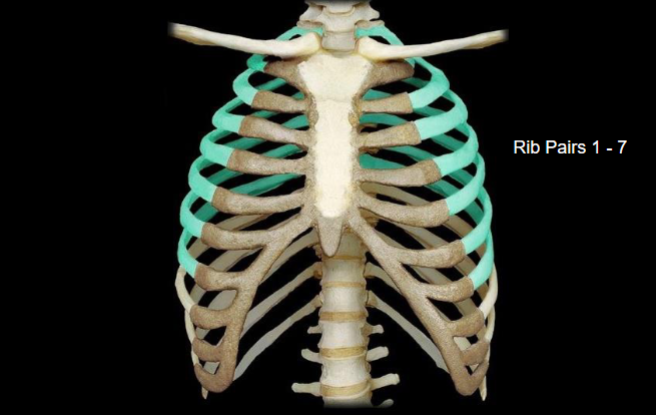

What bone is highlighted in this image?

What type of ribs are highlighted in this image?

vertebrosternal (true) ribs (the spiral looking bones going from behind to the front)